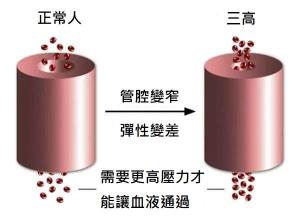

一、改善微循環

地龍蛋白有酶、核酸、微量元素等多種成分,能順暢的進入微血管,使其恢復彈性,從而解除微血管的問題、扭曲變形情況,提高人體自身的抗凝功能,能激活血管內皮細胞的分化特性,打通經脈、促進微血管再生,為心腦組織開辟新的血液通路,修復壞死的腦神經細胞。同時又有助於消除與微循環障礙有關的衰老,提高免疫力。

三、軟化血管

地龍蛋白能促進血管內皮細胞DNA的合成,促進血管壁損傷的修復,軟化血管,恢復血管彈性使血液暢通。

五、雙向調節血管

地龍蛋白通過恢復血管彈性、改善微循環,降低血流外周阻力,通過改善血液質量和外周阻力達致血管暢順。